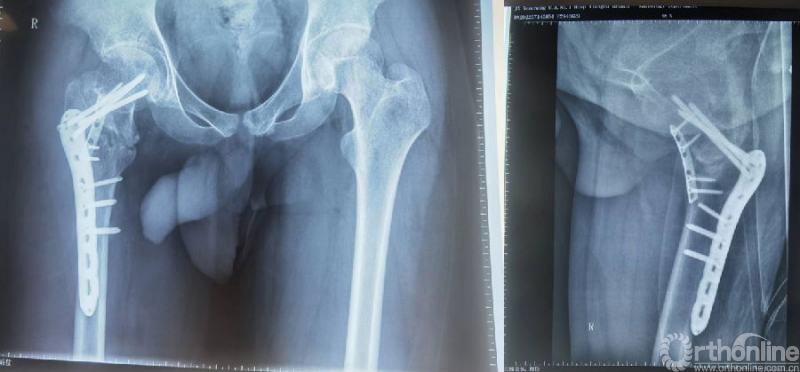

手术过程:

(1)髂骨自体取骨,取适量松质骨;

(2)取出锁定钢板上的第4颗螺钉;

(3)DAA入路,切开关节囊;

(4)彻底刮除骨折断端纤维瘢痕组织;

(5)植入自体松质骨+BMP-2改善局部生物学环境;

(6)植入1/3管形板支撑,改善骨折愈合的生物力学环境。

影像学资料